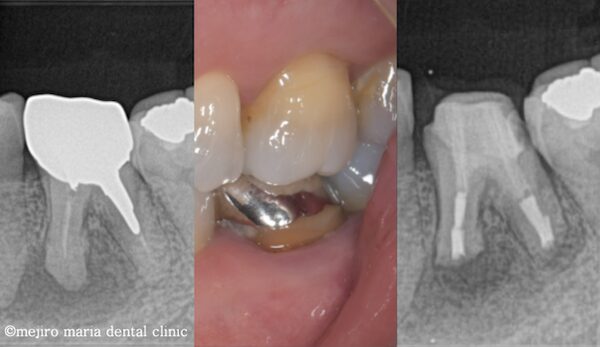

上記のエックス線写真で、術直後に根尖付近に見られた透過像(黒く見える部分)は、3ヶ月後には小さくなり、治癒傾向にあることが確認できます。また、術前に見られた歯周ポケットの改善と瘻孔(フィステル)の消失も確認できます。

歯質が少ない状態ではありますが、術後3ヶ月経過した時点で違和感の消失、病的な歯周ポケットの改善、瘻孔(フィステル)の消失が確認でき、経過は良好です。最終補綴(被せもの)へ移行後も、最低2年間は年1回ほどの経過観察を予定しています。